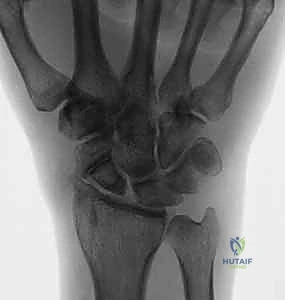

تُعد عملية استئصال القطب البعيد للعظم الزورقي (Excision of the Distal Pole of the Scaphoid) حلاً جراحياً ذكياً ومبتكراً. الفكرة الميكانيكية وراء هذه الجراحة هي: "إذا كان القطب البعيد للعظم الزورقي هو الذي يحتك بعظم الكعبرة ويسبب الألم والخشونة، فلنقم بإزالته مع الحفاظ على باقي هياكل الرسغ".

خطوات العملية الجراحية بالتفصيل:

- التخدير والتحضير: تتم العملية غالباً تحت تخدير موضعي (Block) للذراع أو تخدير عام. يتم استخدام عاصبة (Tourniquet) لمنع تدفق الدم مؤقتاً لضمان رؤية جراحية واضحة تماماً.

- الشق الجراحي: يقوم الدكتور هطيف بعمل شق جراحي صغير ودقيق (حوالي 3-4 سم) في الجهة الظهرية أو الراحية للرسغ، مع مراعاة الحفاظ على الأعصاب الحسية والأوتار المحيطة.

- الوصول إلى العظم الزورقي: يتم فتح كبسولة المفصل بحذر شديد للوصول إلى العظم الزورقي التالف.

- الاستئصال الدقيق: باستخدام أدوات جراحية ميكروسكوبية دقيقة، يتم استئصال حوالي 3 إلى 4 مليمترات من القطب البعيد للعظم الزورقي. هذه الكمية كافية لمنع الاحتكاك مع عظم الكعبرة، وفي نفس الوقت تحافظ على استقرار الأربطة.

- تقييم المفصل: يتم فحص باقي عظام الرسغ للتأكد من عدم وجود خشونة متقدمة في أماكن أخرى.

- الإغلاق والخياطة: تُغلق كبسولة المفصل والجلد بخيوط تجميلية دقيقة لتقليل الندبات، ثم يُوضع الرسغ في جبيرة داعمة.